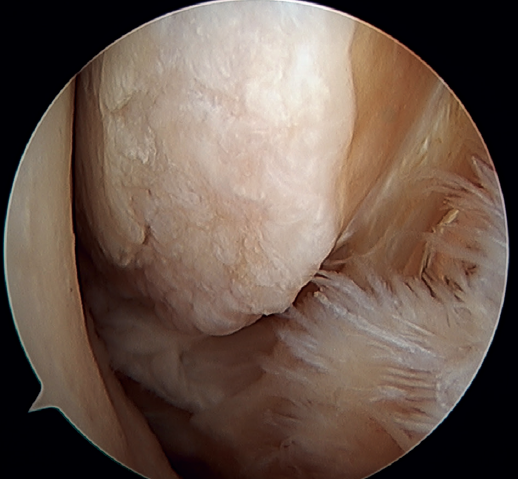

Otro punto de interés es la presencia de os subfibularis; en estos casos, existe la opción de la fijación, si bien no suele ser factible y la mejor opción terapéutica es su exéresis y reconstrucción, debido a la imposibilidad de realizar una reparación directa(60) (Figura 4).

Figura 5. Rotura del ligamento talofibular anterior y del ligamento calcaneofibular con mala calidad tisular del remanente ligamentoso.